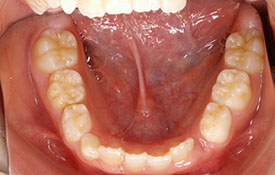

インビザラインの治療例:CASE-2

| プロフィール | 15歳 男性 |

| 所見 | アメリカから転院されて来られた方です。 インビザラインで上下顎の矯正治療を開始し下顎はアメリカで終了しており、上顎のみ治療の後期を担当しました。 アイライナーの装着は、1日平均22時間ほどでした。 |